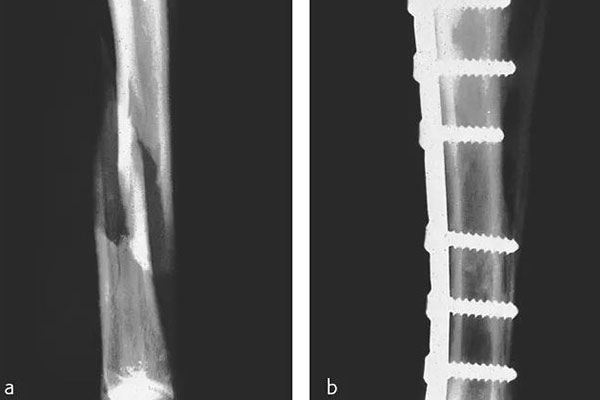

那在檢測(cè)的時(shí)候還需要看到植入物的情況,但由CFPEEK復(fù)合材料制成的零件通常具有放射透性,幾乎無(wú)法通過(guò)X射線(xiàn)檢測(cè)。就通過(guò)添加諸如鉭絲之類(lèi)的X射線(xiàn)散射材料,可以使植入物變得可見(jiàn)??梢钥聪聢D展示了一個(gè)固定骨折骨頭的骨愈合板。可以看出,通過(guò)設(shè)計(jì)已對(duì)放射密度進(jìn)行了定制,以便在盡量減少對(duì)骨折部位遮擋的同時(shí)可視化組件。重要的是,實(shí)現(xiàn)X射線(xiàn)可見(jiàn)性的同時(shí)也能保持清晰的MRI圖像。